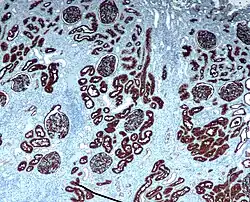

Chromogenic immunohistochemistry of a normal kidney targeting the protein CD10.

Immunohistochemistry is an excellent detection technique and has the tremendous advantage of being able to show exactly where a given protein is located within the tissue examined. It is also an effective way to examine the tissues. This has made it a widely used technique in neuroscience, enabling researchers to examine protein expression within specific brain structures. Its major disadvantage is that, unlike immunoblotting techniques where staining is checked against a molecular weight ladder, it is impossible to show in immunohistochemistry that the staining corresponds with the protein of interest. For this reason, primary antibodies must be well-validated in a Western Blot or similar procedure. The technique is even more widely used in diagnostic surgical pathology for immunophenotyping tumors (e.g. immunostaining for e-cadherin to differentiate between ductal carcinoma in situ (stains positive) and lobular carcinoma in situ (does not stain positive)[19]). More recently, immunohistochemical techniques have been useful in differential diagnoses of multiple forms of salivary gland, head, and neck carcinomas.[20]